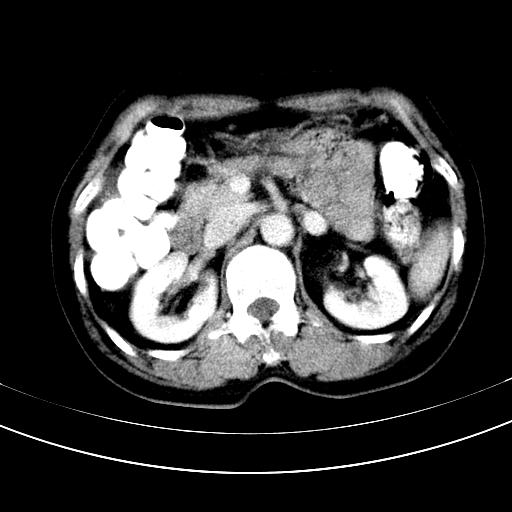

补充强化片

肝左叶及尾叶低密度灶,增强有渐进性明显强化,考虑血管瘤。胃内“充缺”首先要排除异物(食物),变换体位可鉴别。增强时机抓的不好,还应该有延时像。

谢谢楼主的增强片子,平扫没发现左侧肾上腺的问题很不好意思,可惜片子只有门脉期,所以还只有猜,肝脏的病灶在门脉期部分强化,首先考虑为血管瘤(其他的用一种病不好解释)胃要喝水就好了现在不好说是否有问题,左肾上腺的问题考虑是肿瘤。

做了增强后,可以明确胃是没有肿瘤的,肾上腺也没有肿瘤.肝左叶的病灶首先考虑血管瘤,应该再延迟,肝尾状叶的病灶仍不能排除肝癌的可能性.